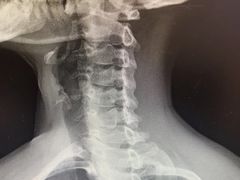

• -上海中医药大学附属曙光医院(东部)

贪捏惹花闯江湖 | 25-02-06